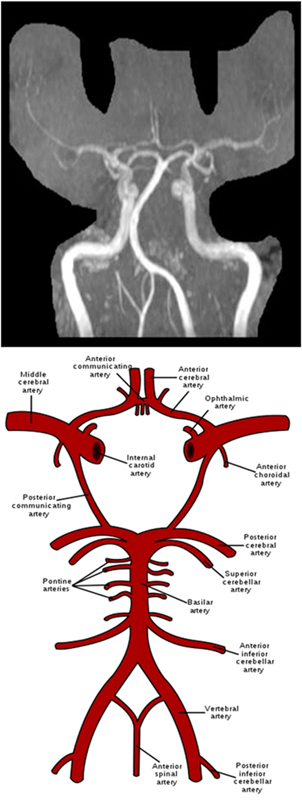

COW 3D TOF 3D FFE 1mm 0mm 20cm MIP COW, Right, Left and Posterior

MRA Brain WO Protocol Image2

MRA Brain WO Protocol Image3